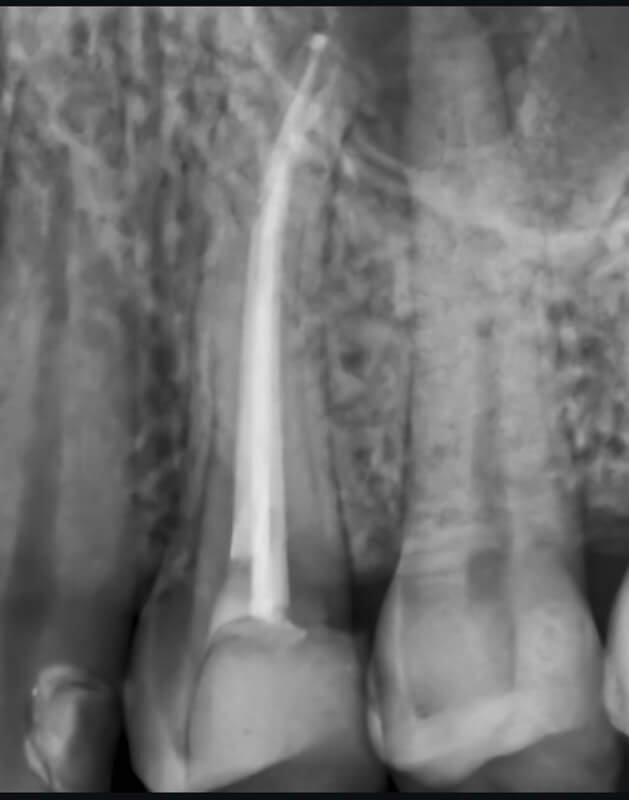

Utilizarea tehnicilor moderne asigură un tratament rapid, precis și confortabil pentru pacient.

Reconstituirea coronară cu materiale de calitate conferă rezistență pe termen lung.